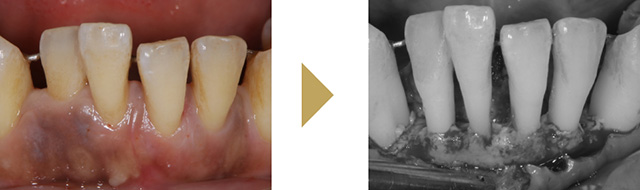

歯周外科治療

麻酔をして少し歯茎を開いてあげると、歯周病菌を目で見て除去することが可能になり、徹底的に歯周病菌を除去できます。また格段に歯周病治療の成績が向上します。条件が揃えば、失ってしまった骨を増やすような再生治療を行うことも可能です。